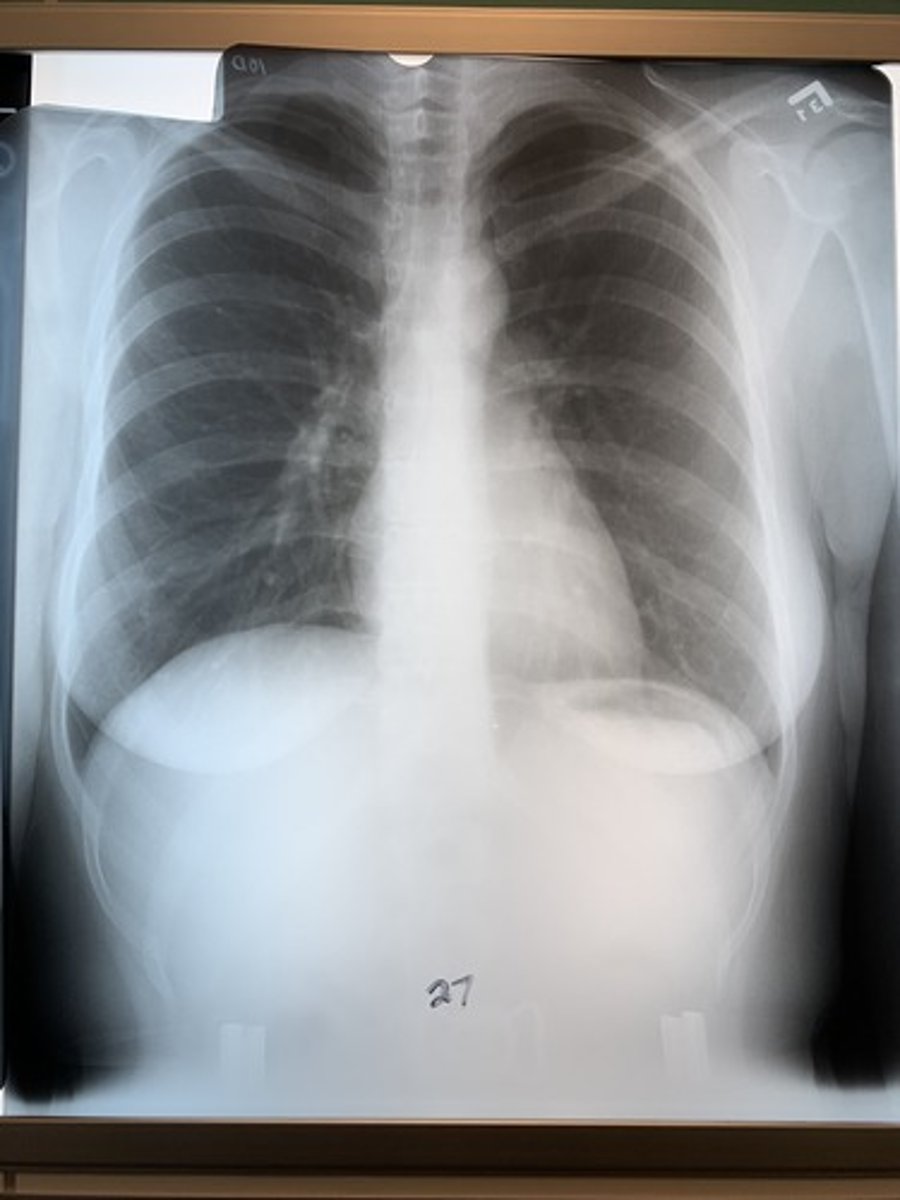

Regarding radiograph 27, is it penetrated?

Penetrated